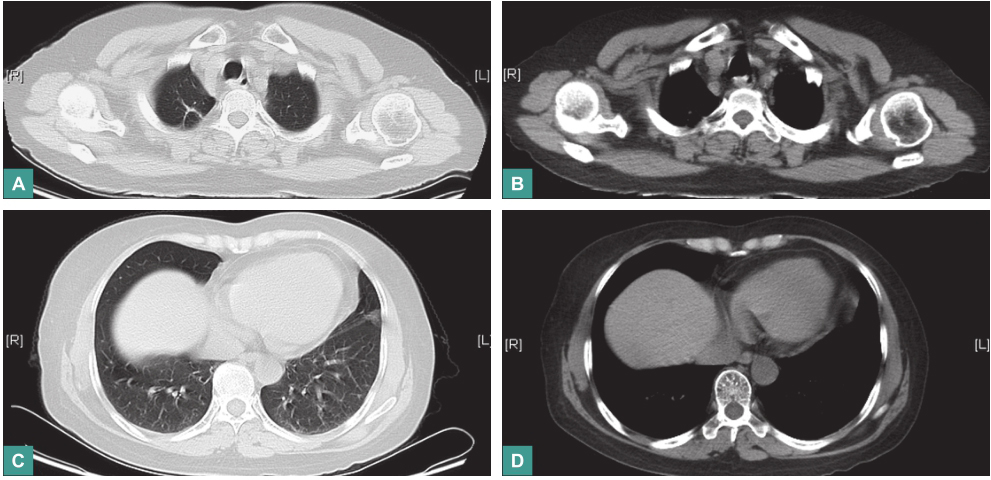

经上述治疗后,患者体温恢复正常,无咳嗽、咳痰、双耳疼痛及面部疼痛,于2016年4月20日出院。出院后,患者于门诊规律随诊,截至2017年3月底,甲泼尼龙减至8mg/d,环磷酰胺为(50mg,每天1次)维持。复查血沉4mm/h,C反应蛋白<0.789mg/L。胸部CT示双肺斑片状、条索影,右肺上叶尖段、双侧肺门区及周围多发结节已吸收(图9)。

图9 胸部CT:肺部多发结节已吸收